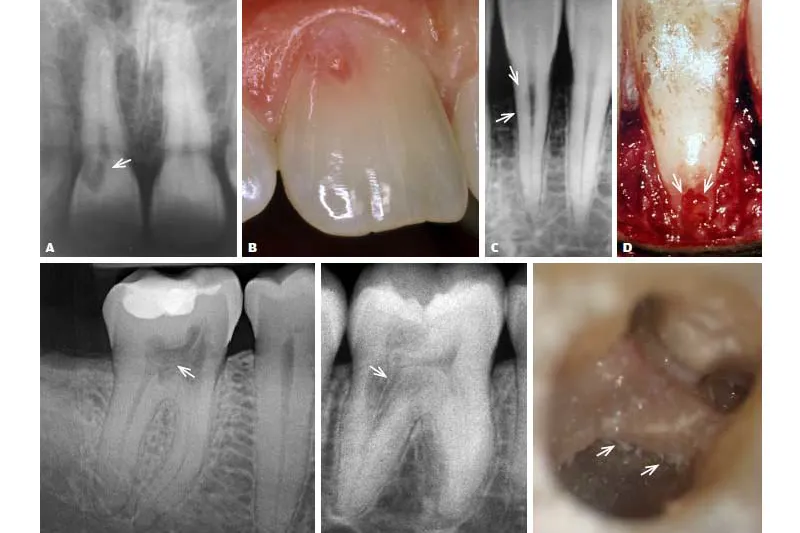

Fire tilfælde af cervikal resorption med stigende kompleksitet svarende til Heithersays klassifikation præsenteres, og hvor endodontiske og kirurgiske behandlingsprincipper benyttes. Ved de fremadskridende stadier er rodbehandling nødvendig udover behandling af resorptionskaviteten.

Four cases of cervical resorption with increasing complexity are reported, following the Heithersay classification, where endodontic and surgical treatment principles have been used. For advanced lesions root canal treatments are needed besides treating the resorption.